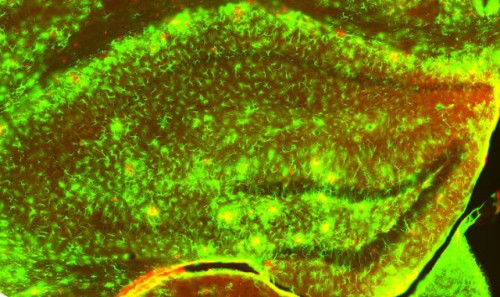

En verde se ve marcado el GFAP y, por tanto, los astrocitos reactivos en las zonas de patología, es decir, donde hay placas amiloides (en rojo). (Foto: Universidad de Barcelona)

En este trabajo, los expertos han estudiado los FNDC generados por los astrocitos, un tipo de células de glía de forma estrellada que se encuentran en el cerebro y en la médula espinal. Los astrocitos se ven afectados por uno de los procesos de neuroinflamación más conocidos del alzhéimer, la astrogliosis, en la que la proteína GFAP es la más alterada. En este contexto, diseñaron un experimento en el que unos ratones modificados genéticamente sufren alzhéimer y también producen FNDC en función de los niveles de GFAP.